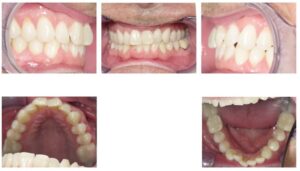

Case 1 – No attachments, lower treatment only (extraction LL2)

| Initial | 6-month progress, 25 aligners |

Case 2 – Attachments on U/L 2s

| Initial | 5-month progress, 14 aligners |